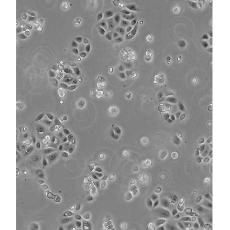

SW 1990

中文名稱 人胰腺癌細胞

生長特性 adhere

形態(tài)特征 epithelial

細胞描述 1978年從胰腺外分泌腺的胰腺腺癌II期患者的脾轉(zhuǎn)移灶中建立了SW 1990細胞株。 報道該細胞的植板率為29%。